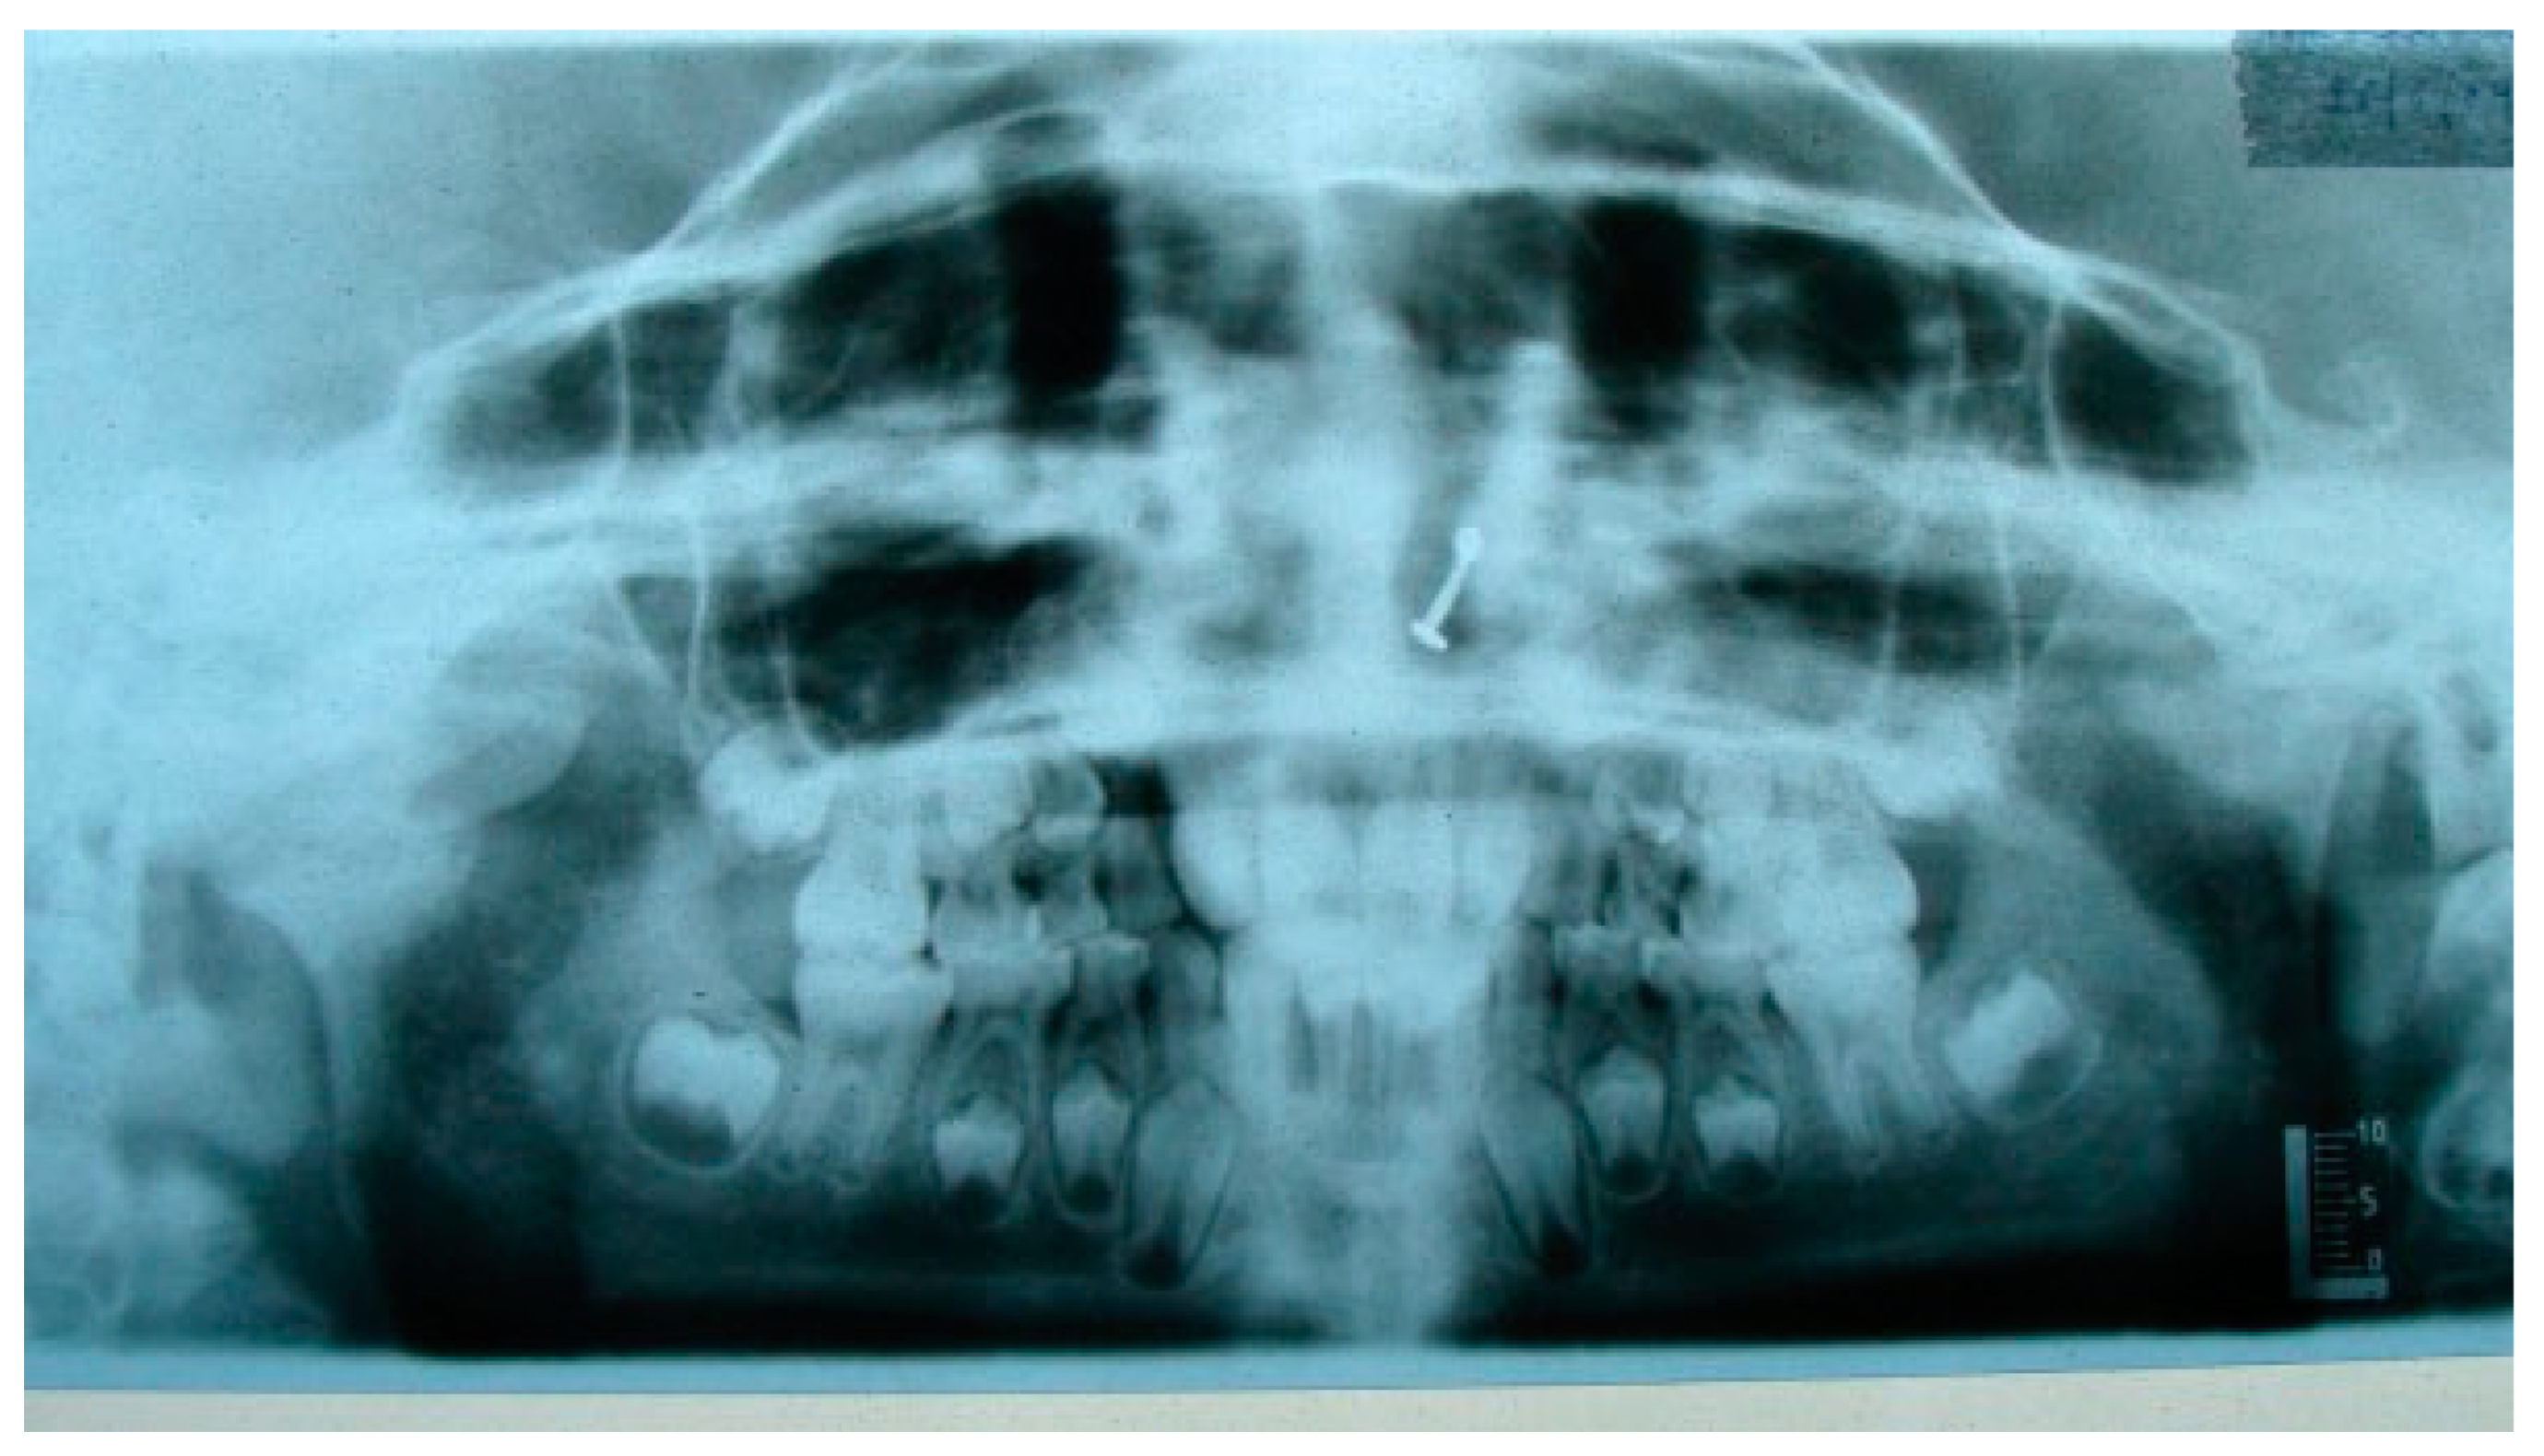

A retrospective study of post–ankylotic TMJ reconstruction of all the patients who underwent surgery for the TMJ ankylosis over a period of 11 years from 2002 to 2013, which were operated by the senior author (Y.B.), was undertaken to evaluate demographics, type of TMJ ankylosis, and modality of post–ankylotic TMJ reconstruction. The following inclusion criteria were considered for enrolling patients in this study: (1) history of traumatic injury to the face or jaws; (2) clinical and radiographic evidence of bony ankylosis at the time of presentation; (3) reconstruction of the TMJ using autogenous or alloplastic material after surgical release of ankylosis. Patients were assessed for (1) maximum interincisal opening pre and post operatively; (2) restored vertical ramal height; (3) occlusion; (4) facial symmetry; and (5) postoperative complications. Radiographic evaluation consisted of both preoperative and postoperative panoramic radiography Orthopentomogram (OPG) (Figure 1 and Figure 2) and CT scans in axial, coronal, and sagittal sections with three-dimensional reconstruction (Figure 3 and Figure 4). Surgical protocol was that the TMJ was approached through the Al-Kayat and Bramley’s incision and at least 2 to 2.5 cm resection of the ankylotic chunk was performed in all our cases. Ipsilateral and contralateral coronoidectomy was performed when required to achieve passive mouth opening. Interpositional arthroplasty was done using various materials such as temporalis fascia, temporalis muscle, and articular disc, whereas joint reconstruction was done using CCG and titanium reconstruction plate with condylar head. Intensive physiotherapy postoperatively was an integral part of protocol.

The unique ability of the CCG to remodel into neocondyle could be well appreciated on the digital OPG and CT scan of the patient. The length and width of the neocondyle was very much comparable to the length of the condyle on the unaffected side at 6 years follow-up. Thus, the neocondyle formed using the costochondral cartilage was identical to the unaffected mandibular condyle both structurally and functionally. Poor socioeconomic conditions and lack of awareness coupled with poor primary health care facilities lead many of these unfortunate patients to live with this debilitating condition well into adulthood. Five such adult patients with age ranging from 17 to 36 years reported to us for treatment of TMJ ankylosis. In all these patients, ankylotic bony mass extends beyond the boundaries of the joint capsule. Alloplastic reconstruction after the release of ankylosis was our method of treatment, although high cost of condylar prosthesis led us to use 2.4 mm condylar head reconstruction plate along with temporalis muscle interpositioning in these patients. Interpositional grafts may fail to restore the ramal height in bilaterally ankylosed adult patients, so alloplastic condylar reconstruction may become the preferred choice. Advantages of alloplastic TMJ reconstruction are that the physical therapy can begin immediately, there is no need for a secondary donor site, surgery time is decreased, and alloplasts can be constructed in such a way as to mimic the normal anatomic contours of the structures they are to replace [17,18]. Wolford and Karras have suggested autologous fat transplantation as a useful adjunct to prosthetic TMJ reconstruction, as it minimizes the occurrence of excessive joint fibrosis, heterotopic calcification, and improves the range of motion [19]. However, they have categorically stated in their discussion that heterotopic bone formation is seen in multiple operated joints and joints with previously failed alloplastic implants. Another method to combat heterotopic bone formation is the use of 10 Gy of irradiation in five fractionated daily doses in the immediate postoperative period [20]. In our series, none of the patients reported with heterotopic bone formation possibly because they had undergone a single surgical procedure for managing TMJ ankylosis. The risk of fossa perforation could have been taken care by interpositioning of temporalis muscle in all these patients.

Figure 2. Postoperative OPG at 6 years of follow-up (black arrow depicting CCG graft with temporalis muscle interpositioning with respect to right temporomandibular joint).